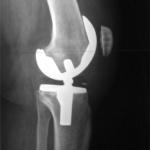

Medical Decision making

In medicine’s recent past, Dr. Welby could be counted on to dispense sage fatherly advice. Fast forward a decade or two, and Dr. Grey often lays out the options while addressing their and their patient’s angst.